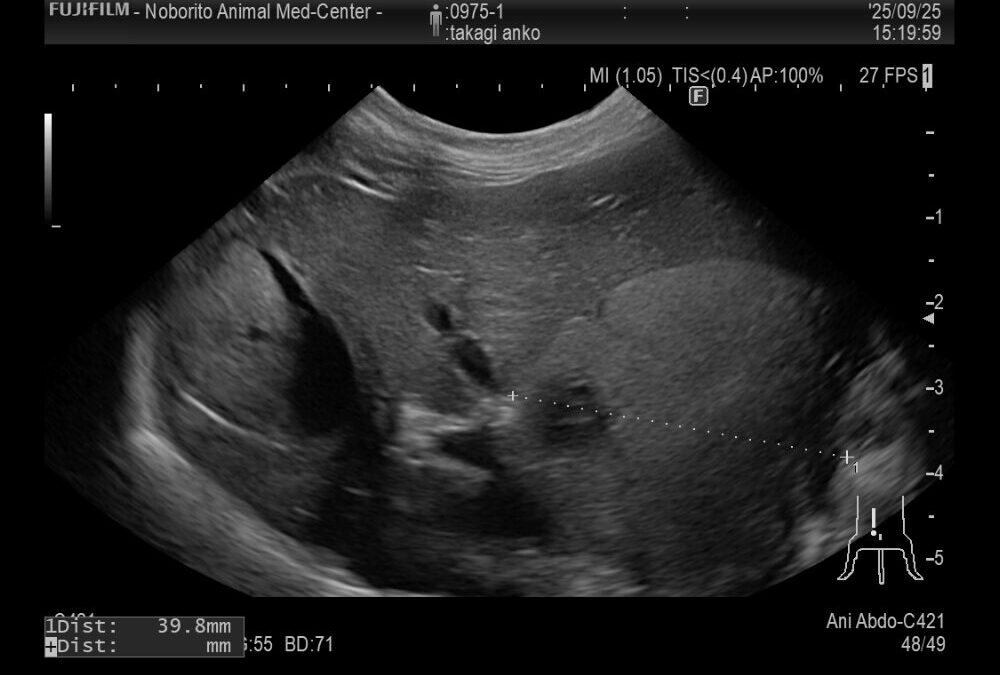

症例は9歳の柴犬でかかりつけにて肝臓に腫瘍が見つかったが、手術が難しいとのことで来院されました。

超音波で確認すると肝臓の基部に腫瘍が認められました。犬の肝臓腫瘍は肝細胞癌の可能性が高いので、摘出を行いました。